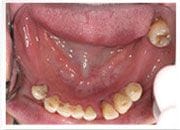

林小姐求診時, 下顎牙齒嚴重牙周病, 咀嚼功能喪失

下顎植牙假牙完成照片, 林小姐重新獲得一副新的牙齒, 從此不需擔心蛀牙, 也沒有牙周病的問題